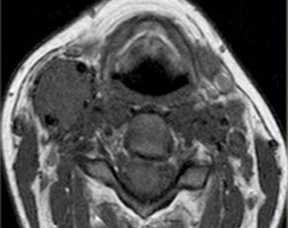

(Слева) МРТ Т1ВИ FS с КУ, аксиальная проекция. В задних отделах подподъязычного сонного пространства расположено образование округлой формы. Шваннома симпатического ствола смещает и сонную артерию, и внутреннюю яремную вену кпереди. Одновременное смещение обоих сосудов сонного пространства весьма характерно для шванномы симпатического ствола.

(Справа) МРТ Т1ВИ FS c КУ, коронарная проекция. Шваннома симпатического ствола, расположенная в сонном пространстве. Опухоль неравномерно накапливает контрастное вещество. Участки кистозного перерождения в крупных шванномах встречаются достаточно часто.